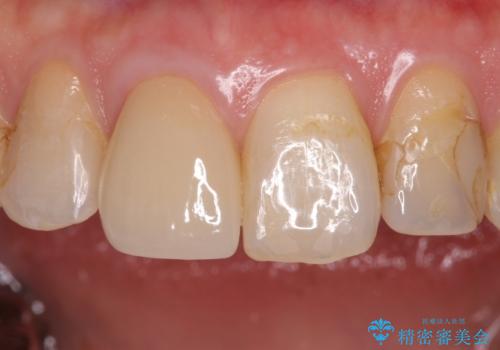

- 左上5 セラミックインレー/77,000円費用は治療当時の料金となります

適合の良いインレーは段差がない上にセラミックは汚れがつきにくい材料であるため今後の虫歯発生リスクを抑えることに繋がります。